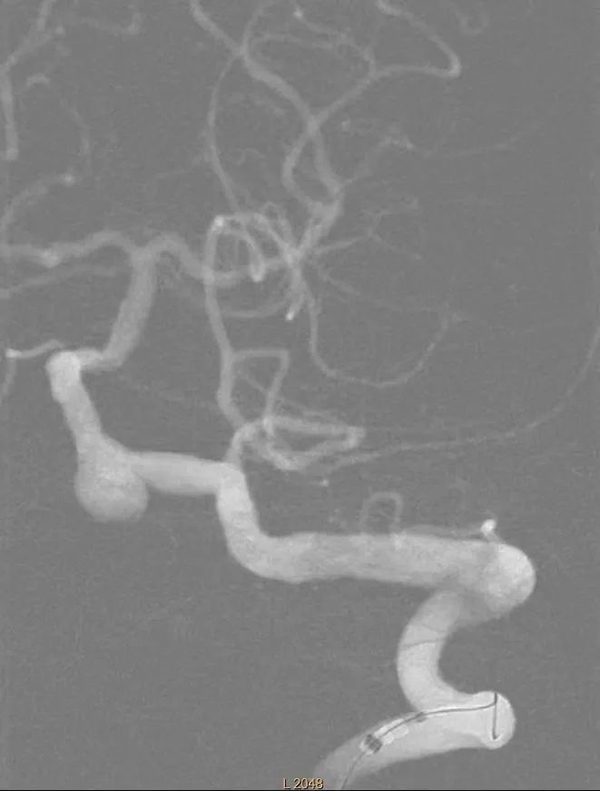

在市十院介入科团队、神经内科团队和医大二院神经外科团队共同努力下手术非常顺利,术中选用5F猪尾造影管开始进行主动脉弓造影和旋转造影见椎动脉V4段动脉瘤。选取工作角度,应用导丝超选至基底动脉,选用3.5*20mm pipeline II支架,定位释放。术后造影显示瘤体内血流灌注延迟缓慢。

椎动脉及后循环造影